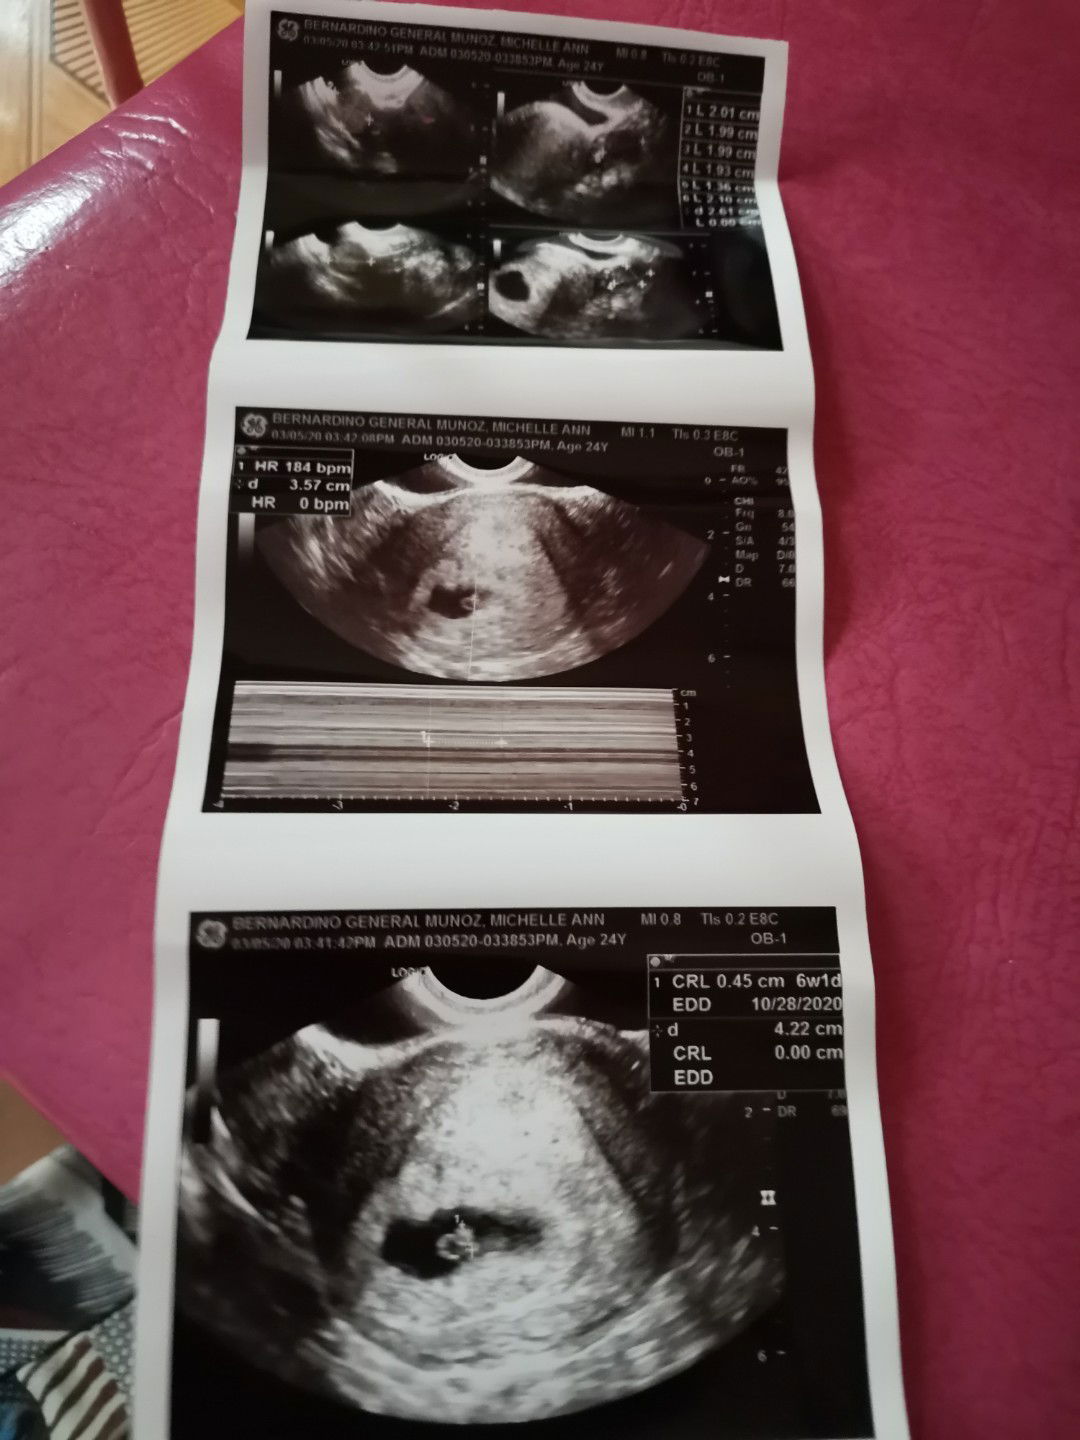

I had my first transv ultrasound last week. Based sa OB sonologist, my heartbeat na daw by just looking at the monitor. I wasn't aware na need pala iparinig saken ung heartbeat, pinakita lang din saken ung monitor. I was 6 weeks and 1 day at the time of the scan. Nakitaan din na hindi ako nakaihi, pero ok lang daw since kita naman ung baby. Normal lang po ba gnyang itsura ng 1st ultrasound?